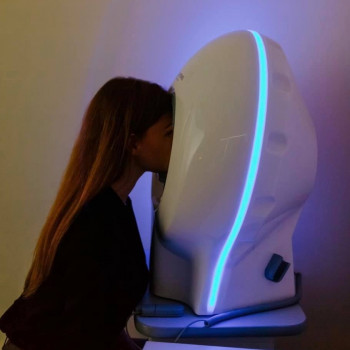

- Аппаратное лечение зрения у ребенка